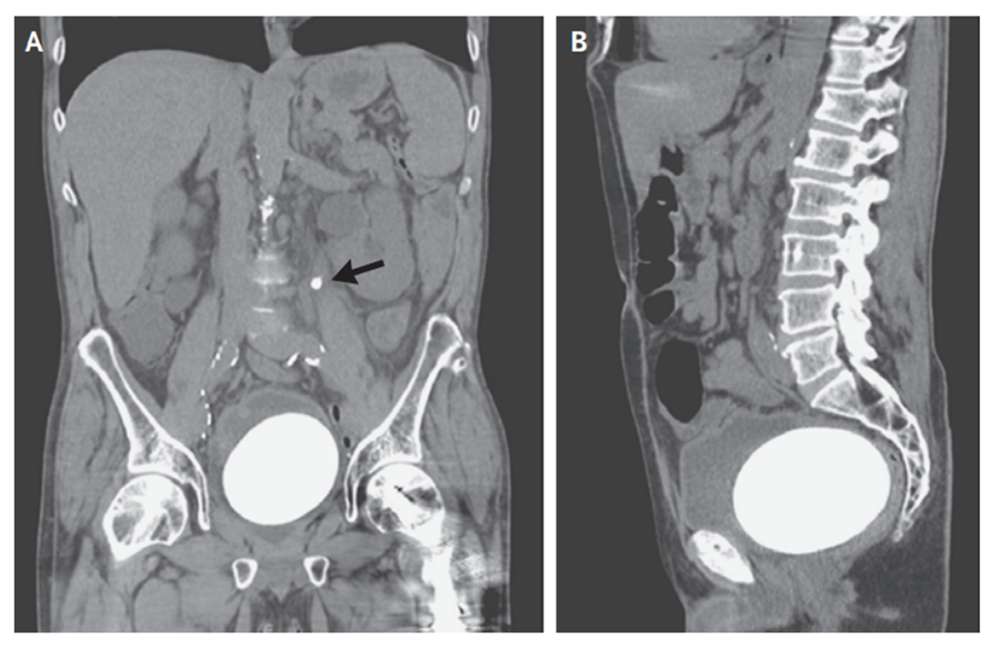

Tại đây, các bác sĩ thực hiện thủ thuật chụp cắt lớp, và kết quả thu được khiến họ nhanh chóng thực hiện phẫu thuật.

Hình chụp X-quang của bệnh nhân

Theo kết quả chụp, họ nhận thấy một viên sỏi thận khá nhỏ trong niệu quản trái (ống dẫn tiểu). Nhưng quan trọng hơn, bàng quang của ông chứa một cục sỏi khổng lồ, to như quả trứng chim đà điểu. Đó là sỏi bàng quang.

Sau khi phẫu thuật, cục sỏi lấy ra có kích cỡ 12 x 9,5 (cm), và chỉ thiếu 1,3 lạng nữa là tròn 1kg. Đây được xem là một trong những cục sỏi "vĩ đại" trong lịch sử, dù chưa phải là lớn nhất.